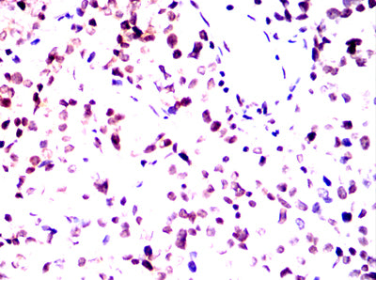

IHC    1/200 - 1/1000